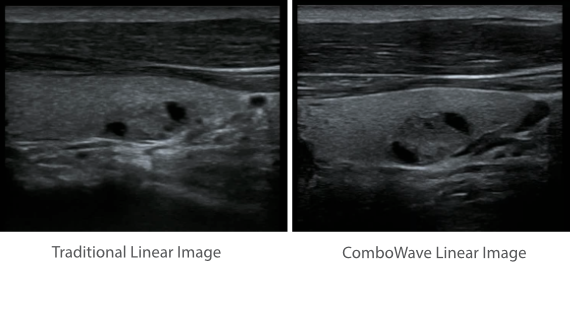

Based on the deep insights of customer needs, the DC-60 ECHO with X-Insight is designed to deliver high efficiency with precision imaging, which is empowered by eXpress Clarity, eXceptional Intelligence and eXceeding Experience.